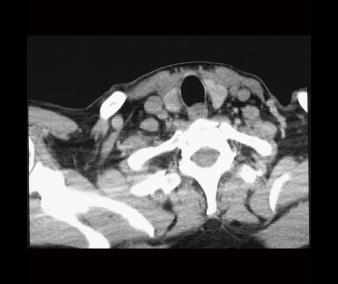

RadLab4CT02 RadLab4CT01

Labels off SCM m

carotid a scalene mm carotid a

strap mm

SCM m esophagus thyroid gland

esophagus

int jugular v vagus n

vertebral a

int jugular v thyroid longus colli

longus colli

scalene mm

vagus n

Normal CT review: Slices 9 & 10